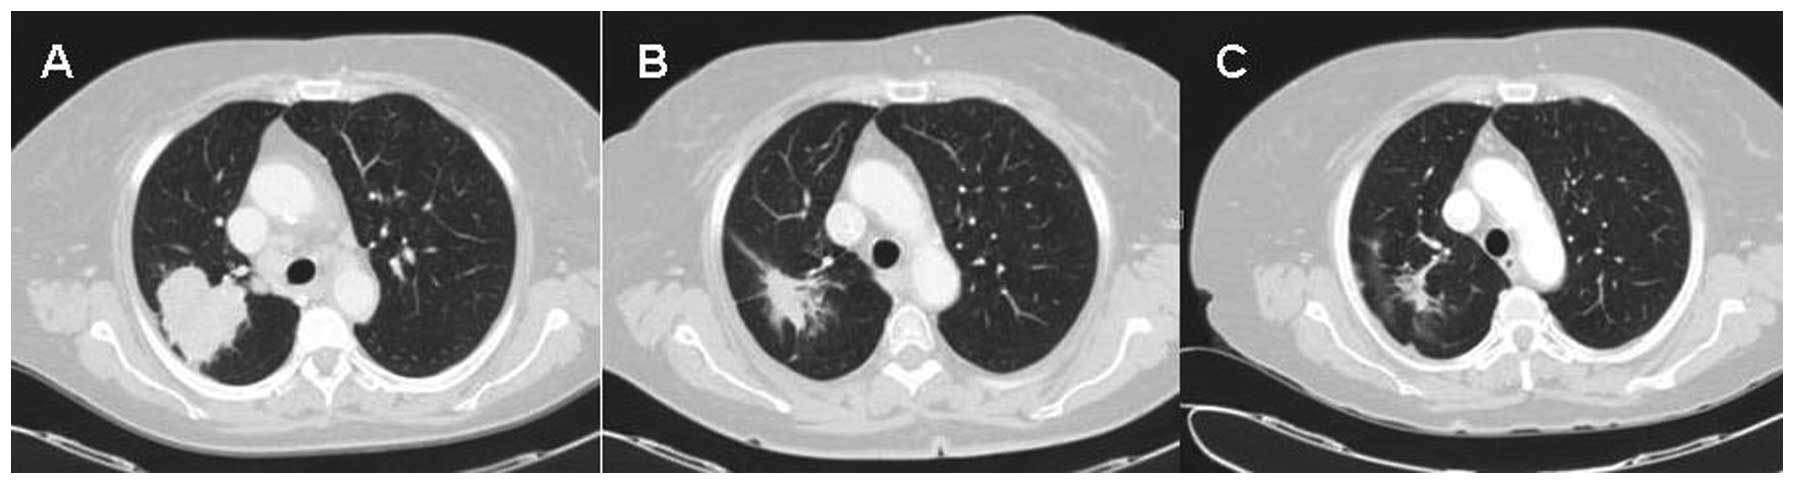

Achievable Complete Remission Of Advanced Non Small Cell Lung Cancer Case Report And Review Of The Literature

www.wjgnet.com